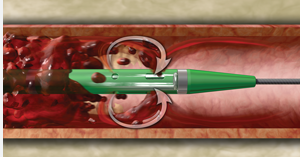

专用导管(CATHEXTRACTOR Catheter):非常细长柔软的管子,头端有一个独特的自膨胀设计的分离器 (Separator)。导管被送到血栓内部。

分离器(SEPARATOR):一个位于导管内的小型金属丝装置,可以前后移动,其作用是物理性地破碎血栓并防止导管头端被大块血栓堵塞,从而保持抽吸通道的持续畅通。